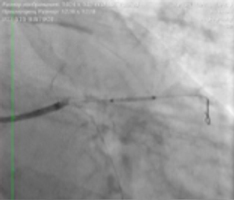

— Мы приняли решение о проведении эндоваскулярной коррекции этого поражения. С помощью двух баллоных катетеров диаметром 2,5 мм была выполнена предварительная дилатация стеноза ствола левой коронарной артерии, устьев огибающей артерии и передней нисходящей артерии по методике «целующихся баллонов». Это одновременное раздувание двух баллонов на бифуркации — успешно применяемое нами прогрессивное техническое новшество. Затем выполнено стентирование по методу culotte с выходом в переднюю нисходящую и огибающую артерии. На контрольной ангиограмме был выявлен критический стеноз в проксимальной трети передней нисходящей артерии, который ранее был маскирован основным поражением. Был стентирован участок в проксимальной трети. На контрольной ангиограмме кровоток в левой коронарной артерии по шкале TIMI — III, что означает оптимальный результат стентирования. Зон диссекций и резидуальных стенозов нет.

![]() Имплантация стента в проксимальной трети передней нисходящей артерии |